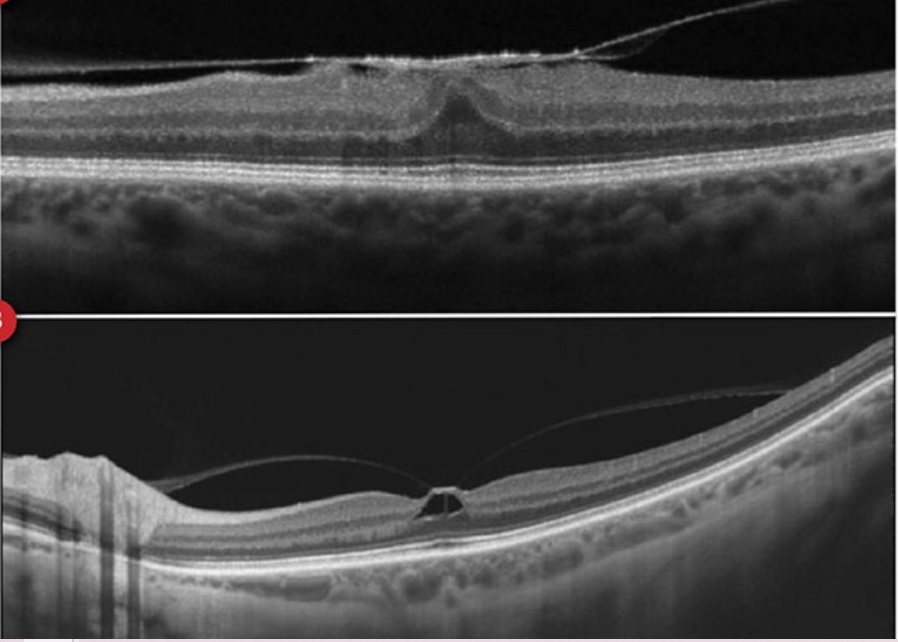

Qual é a classificação do Buraco de Macula?

Classificação de Gass

Estágio 1: Buraco macular iminente

- 1a: Pseudocisto foveal

- 1b: Descontinuidade da retina externa (até 300 micrômetros)

Estágio 2: BM<400 micrômetros + Hialóide aderida à fóvea

Estágio 3: BM > 400 micrômetros + Hialóide solta da fóvea mas permanece aderida ao disco

Estágio 4: BM + DVP completo